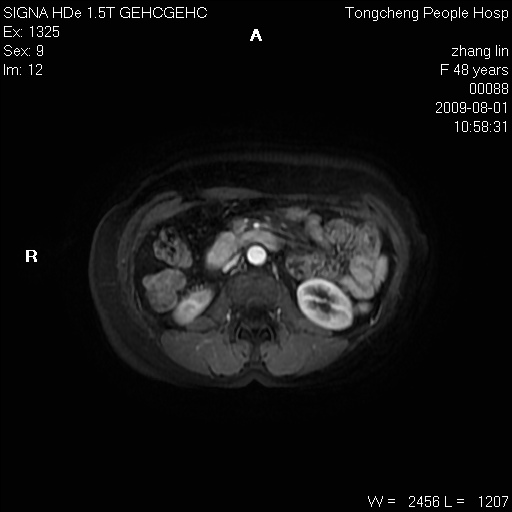

女,48岁。健康体检,彩超发现右肾占位性病变。平素健康。

临床诊断:右肾占位性病变,性质待定(囊肿?肿瘤?)。

上中腹部mr平扫+增强扫描,图像如下:

右肾上极见一类圆形病灶,t1wi呈等信号t2wi呈等高混杂信号,三期增强无强化,边界清---考虑囊肿出血。

同反相位均表现为等信号,病变无强化,考虑含蛋白的囊肿可能,弥散加权相或许有些帮助,

慢性胆囊炎